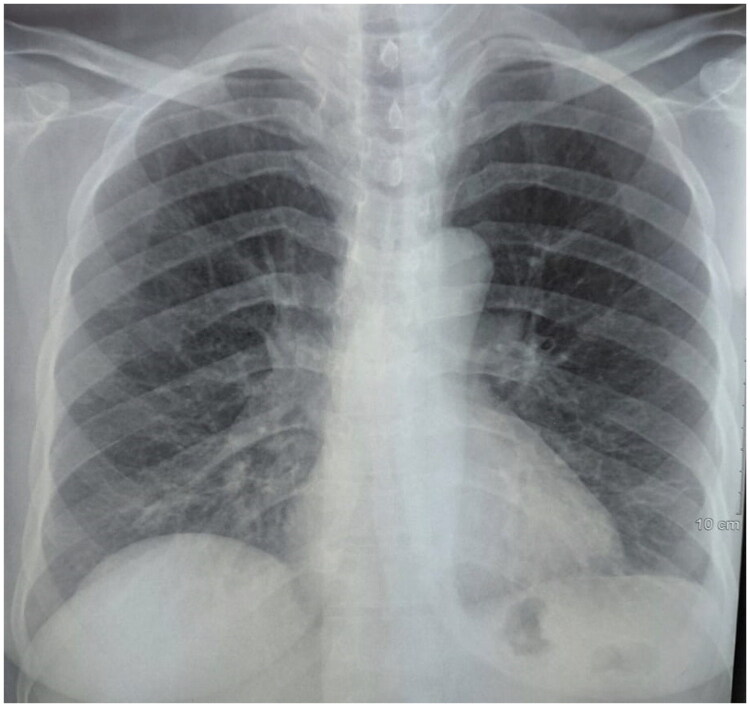

Chylothorax is an uncommon cause of pleural effusion, most often associated with malignancy, trauma, or thoracic duct obstruction. Its occurrence following SARS-CoV-2 infection is exceptional. The present case report describes a 53-year-old woman who was admitted to the pneumology department complaining of chronic dry cough with a medical history of type II diabetes and SARS-CoV-2 infection one month ago. Physical examination revealed decreased vesicular breath sounds at the left lung base. A chest X-ray revealed a left pleural effusion and thoracentesis confirmed chylothorax. This case highlights chylothorax as a rare but possible complication of COVID-19, potentially caused by inflammation and thoracic duct disruption in the absence of thrombosis. It emphasizes the importance of considering chylothorax in the differential diagnosis of unexplained pleural effusions following SARS-CoV-2 infection.